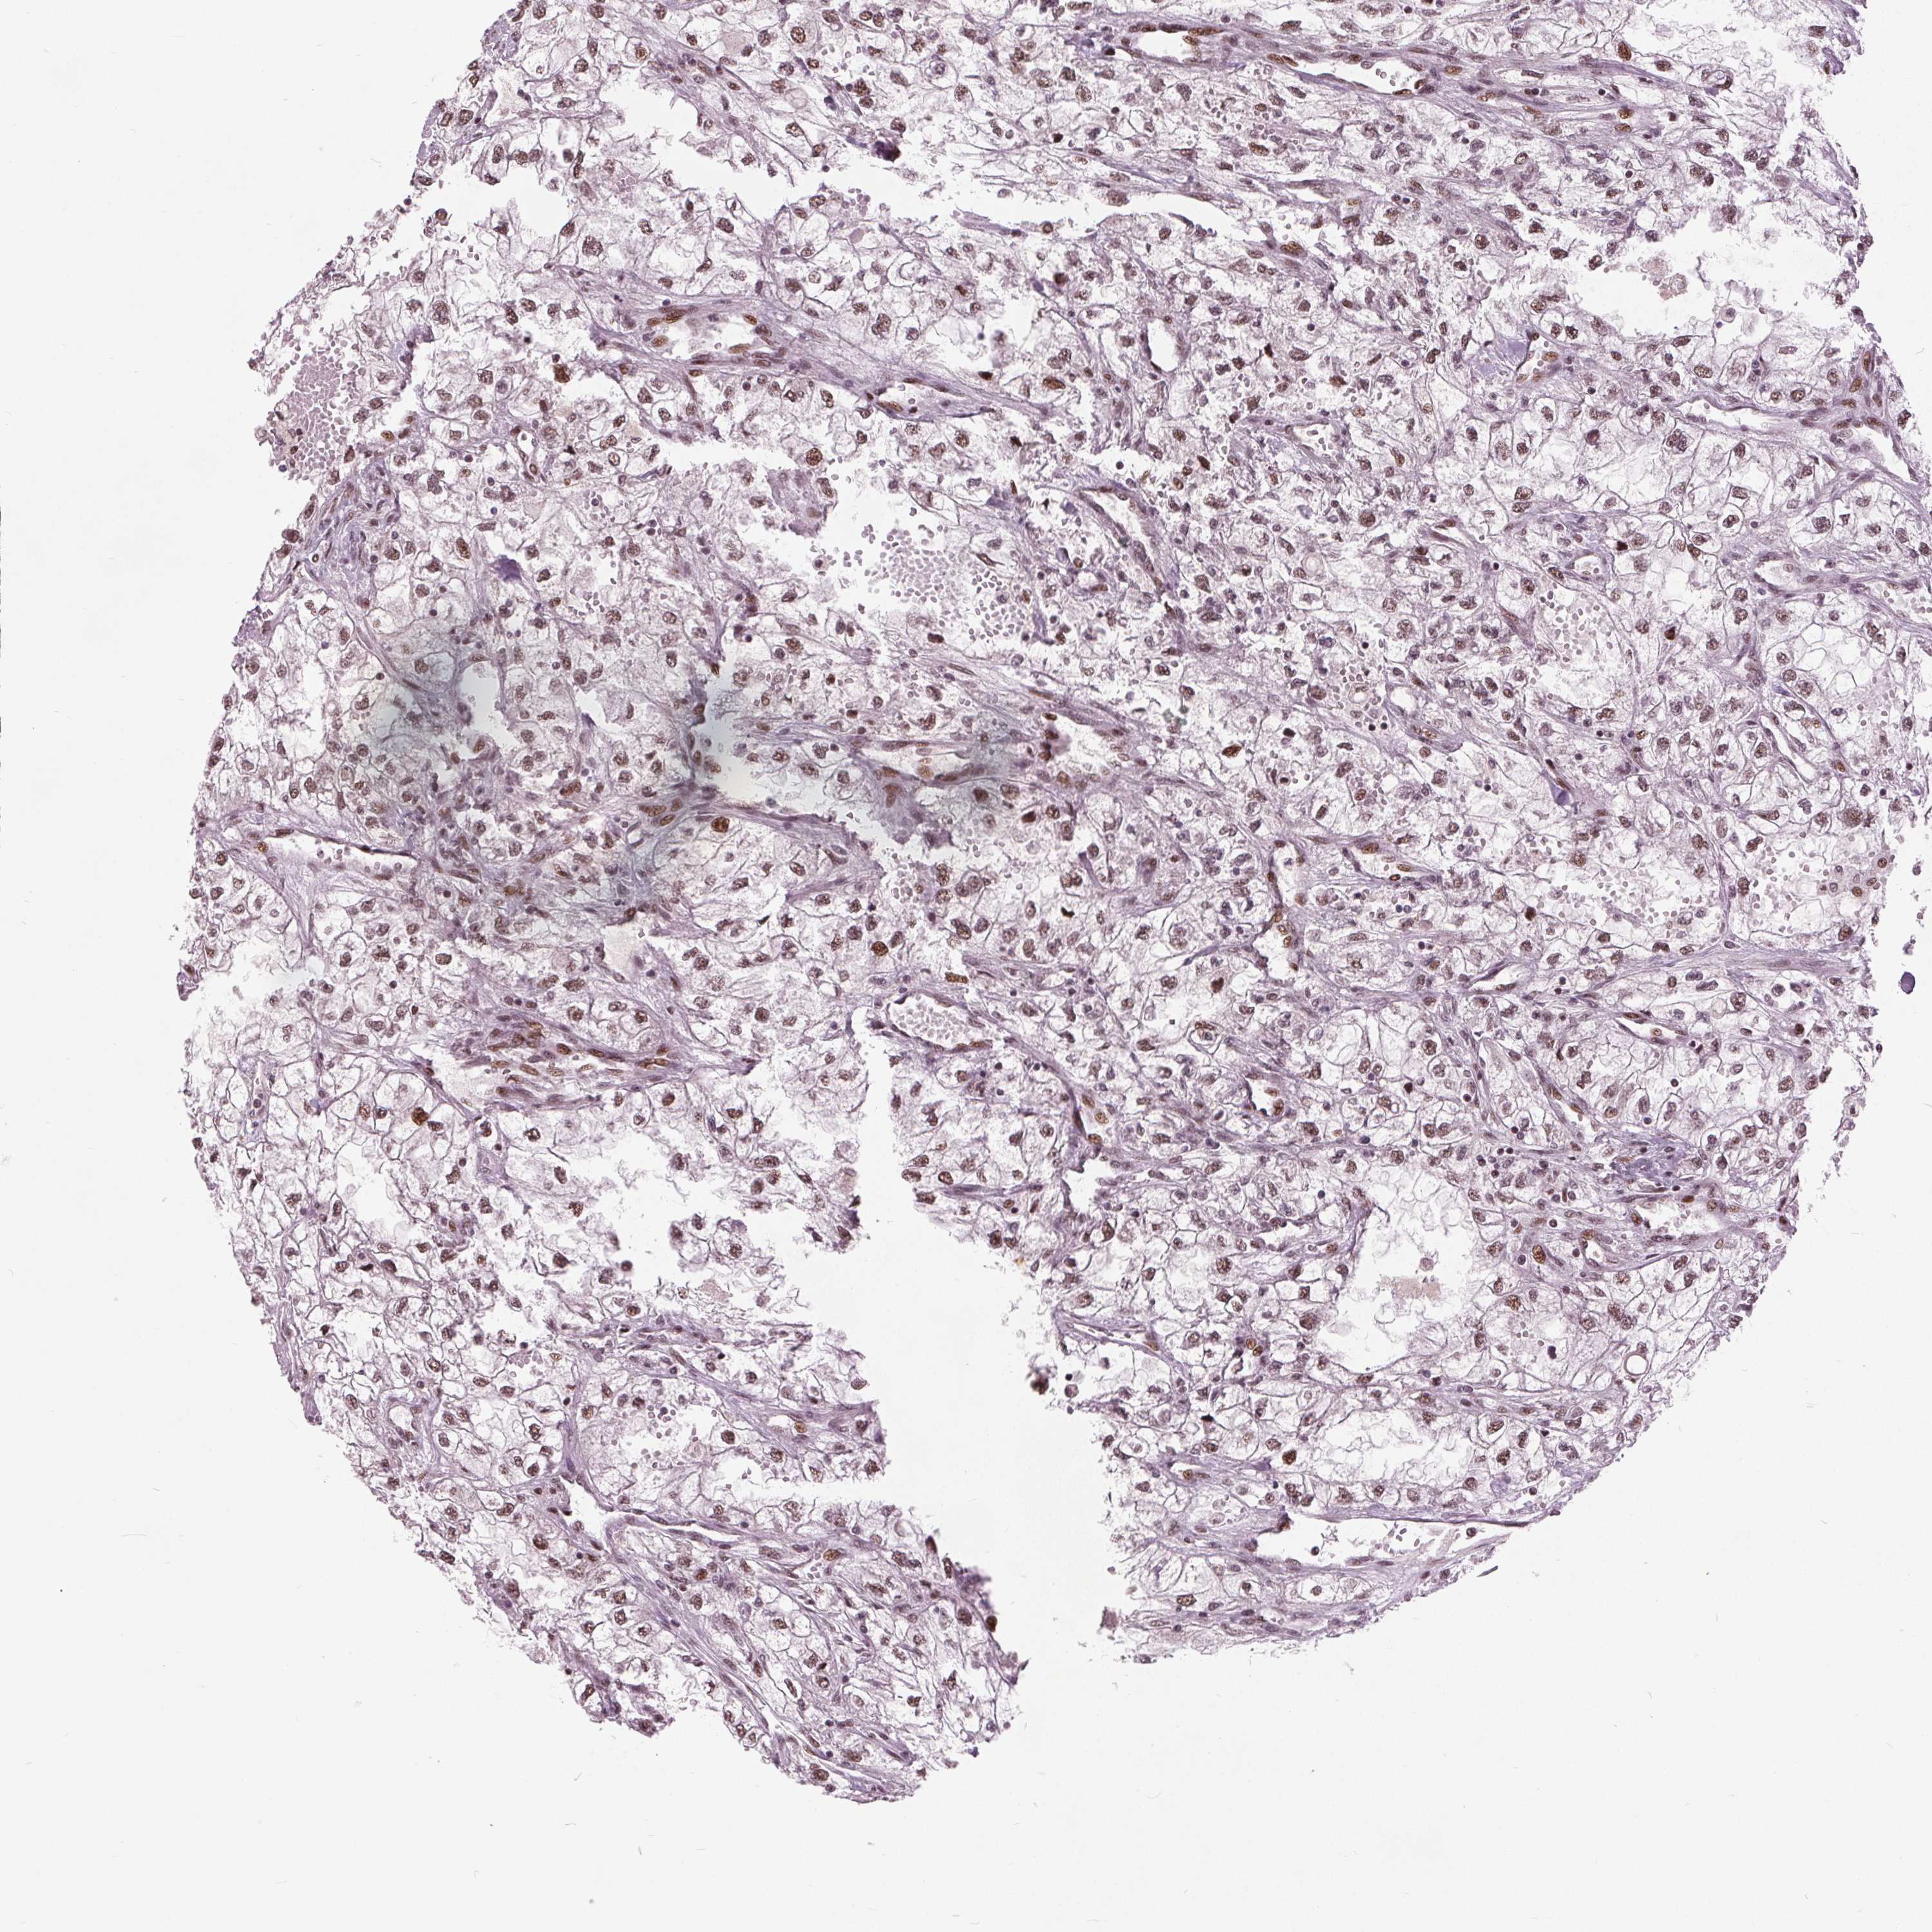

KIDNEY RENAL PAPILLARY CELL CARCINOMA (TCGA) - Interactive survival scatter ploti

The Survival Scatter plot shows the clinical status (i.e. dead or alive) for all individuals in the patient cohort, based on the same data that underlies the corresponding Kaplan-Meier plots. Patients that are alive at last time for follow-up are shown in blue and patients who have died during the study are shown in red.

The x-axis shows the expression levels (FPKM) of the investigated gene in the tumor tissue at the time of diagnosis. The y-axis shows the follow-up time after diagnosis (years). Both axes are complimented with kernel density curves demonstrating the data density over the axes. The top density plot shows the expression levels (FPKM) distribution among dead (red) and alive patients (blue). The right density plot shows the data density of the survived years of dead patients with high and low expression levels respectively, stratified using the cutoff indicated by the vertical dashed line through the Survival Scatter plot. This cutoff is automatically defined based on the FPKM cutoff that minimizes the p-score. The cutoff can be changed by dragging the vertical line or by entering a cutoff value in the square labeled "Current cut-off".

Under the Survival Scatter plot the p-score landscape (black curve; left axis) is shown together with dead median separation (red curve; right axis). Dead median separation is the difference in median mRNA expression between patients who have died with high and low expression, respectively. It is calculated as follows: median FPKM expression of dead patients with high expression - median FPKM expression of dead patients with low expression. This is intended to aid the user in visually exploring custom cutoffs and the associated p-scores and dead median separation.

Individual patient data is displayed and can be filtered by clicking on one or more of the category buttons on the top of the page. Categories describing expression level and patient information include: high, low, alive, dead, female, male and tumor stages. The scale of the x-axis can be toggled between linear and log-scale by clicking on the "x log" button. Mouse-over function shows TCGA ID, patient information and mRNA expression (FPKM) for each patient.

& Survival analysisi

Kaplan-Meier plots summarize results from analysis of correlation between mRNA expression level and patient survival. Patients were divided based on level of expression into one of the two groups "low" (under cut off) or "high" (over cut off). X-axis shows time for survival (years) and y-axis shows the probability of survival, where 1.0 corresponds to 100 percent.

TTC34 is not prognostic in Kidney Renal Papillary Cell Carcinoma (TCGA)